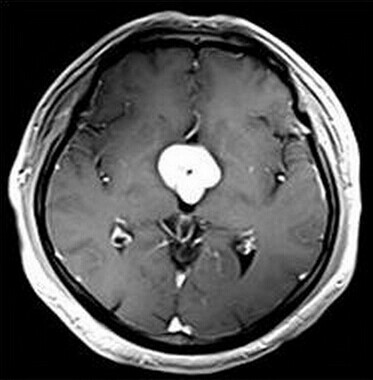

患者:男,50岁,记忆力下降1月余,双眼视力下降,反应减慢。

【正确答案】D 胶质瘤(第三脑室脊索样胶质瘤)

第三脑室脊索样胶质瘤的特征性表现是:

(1)见于成人,边界清楚,位于第三脑室前部;

(2)T1WI上为低信号,T2WI上呈明显高信号;

(3)增强后明显强化;

(4)肿块累及视交叉及下丘脑,但不浸润周围脑实质。